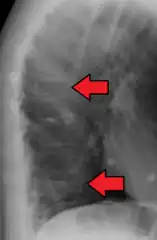

A compression fracture is a collapse of a vertebra. It may be due to trauma or due to a weakening of the vertebra (compare with burst fracture). This weakening is seen in patients with osteoporosis or osteogenesis imperfecta, lytic lesions from metastatic or primary tumors,[1] or infection.[2] In healthy patients, it is most often seen in individuals suffering extreme vertical shocks, such as ejecting from an ejection seat. Seen in lateral views in plain x-ray films, compression fractures of the spine characteristically appear as wedge deformities, with greater loss of height anteriorly than posteriorly and intact pedicles in the anteroposterior view.[3]

Compression fractures are usually diagnosed on spinal radiographs, where a wedge-shaped vertebra may be visible or there may be loss of height of the vertebra. In addition, bone density measurement may be performed to evaluate for osteoporosis. When a tumor is suspected as the underlying cause, or the fracture was caused by severe trauma, CT or MRI scans may be performed.